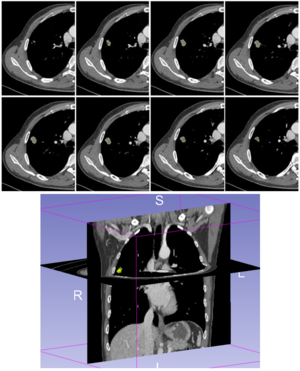

Publication: IEEE Trans Biomed Eng. 2017 Sep;64(9):2134-41. PMID: 27959795 Authors: Baumgarten C, Zhao Y, Sauleau P, Malrain C, Jannin P, Haegelen C. Institution: Signal and Image Processing Laboratory, Department LTSI , University of Rennes, France. Abstract: Objective: Subthalamic nucleus deep brain stimulation (STN DBS) is limited by the occurrence of a pyramidal tract side effect (PTSE) induced by electrical activation of the pyramidal tract. Predictive models are needed to assist the surgeon during the electrode trajectory preplanning. The objective of the study was to compare two methods of PTSE prediction based on clinical assessment of PTSE induced by STN DBS in patients with Parkinson's disease. Methods: Two clinicians assessed PTSE postoperatively in 20 patients implanted for at least three months in the STN. The resulting dataset of electroclinical tests was used to evaluate two methods of PTSE prediction. The first method was based on the volume of tissue activated (VTA) modeling and the second one was a data-driven-based method named Pyramidal tract side effect Model based on Artificial Neural network (PyMAN) developed in our laboratory. This method was based on the nonlinear correlation between the PTSE current threshold and the 3-D electrode coordinates. PTSE prediction from both methods was compared using Mann-Whitney U test. Results: 1696 electroclinical tests were used to design and compare the two methods. Sensitivity, specificity, positive- and negative-predictive values were significantly higher with the PyMAN method than with the VTA-based method (P < 0.05). Conclusion: The PyMAN method was more effective than the VTA-based method to predict PTSE. Significance: This data-driven tool could help the neurosurgeon in predicting adverse side effects induced by DBS during the electrode trajectory preplanning. |

Pre-operative registration between the ParkMedAtlis atlas and the patient’s T1 and T2 weighted MRI. Top left: axial view; top right: antero-superior left three-dimensional view of the cerebral sulci and the segmented basal ganglia, down left; parasagittal view; down right: coronal view. The red dot and line are the preplanned trajectory few days before the surgery to implant an electrode in the left subthalamic nucleus. A: anterior; P: posterior; L: left; R: right; S: superior; I: inferior. Amygdala (light pink), hippocampus (dark pink), putamen (violet), medial pallidum (orange), lateral pallidum (green), caudate nucleus (light blue), thalami (yellow), substantia nigra (grey), subthalamic nucleus (light orange), red nucleus (red), ventricles (dark blue). |